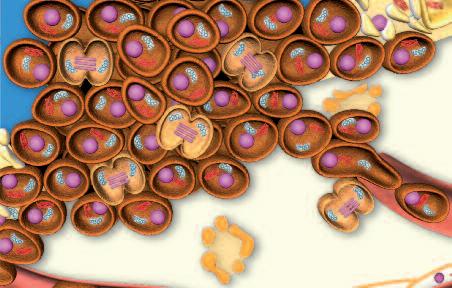

Normalmente, le cellule del nostro corpo sono inserite in una rete di collagene e di altre molecole del tessuto connettivo che le mantengono al loro posto. Affinché le cellule tumorali possano crescere, divenendo un tumore, e possano diffondersi in tutto il corpo, è necessario fendere questo isolamento del tessuto connettivo. A questo fine, ogni cellula del cancro produce ‘forbici biologiche’, ovvero degli enzimi proteolitici in grado di digerire il tessuto connettivo che circonda le cellule tumorali.

Le cellule tumorali non producono questi enzimi distruttivi solo per un breve lasso di tempo, ma durante tutta la loro esistenza. Dal momento che le cellule tumorali sono, per loro natura, immortali, un tumore in fase di crescita potrebbe essere descritto come una malattia che poco a poco digerisce il corpo dall'interno.

La pagina a fianco mostra l'immagine di una cellula tumorale reale, visualizzata al microscopio elettronico, che ingrandisce questa cellula 6500 volte rispetto alle sue normali dimensioni. Questo tipo di cellula prende il nome di carcinoma, cioè derivante da cellule epiteliali, il tipo di cellule che rivestono sia le superfici interne (polmoni, intestini) che esterne (pelle) del corpo.

Grazie a questo ingrandimento si possono identificare chiaramente alcune delle caratteristiche di tutte le cellule tumorali: a) l'enorme nucleo cellulare dalla forma insolita che spiega la loro grande capacità di riprodursi e b) la struttura non uniforme, complessa della superficie cellulare, che riflette una forte attività di secrezione di sostanze prodotte dalle cellule tumorali.

Una delle più importanti molecole secrete dalle cellule tumorali in grandi quantità sono gli enzimi a ‘forbice’ che digeriscono il collagene. Sono aggiunti graficamente a questa immagine, sotto forma di strutture simili ad un ‘pacman’ rosso.

Una volta che le cellule tumorali producono enzimi a ‘forbice biologica’ non hanno più barriere e possono invadere e ‘digerire’ lentamente la struttura di ogni organo del corpo.

Questo vale anche per le cellule leucemiche. Una caratteristica di questa forma di tumore del sangue è l’eccesso di produzione di globuli bianchi, i pazienti affetti da leucemia muoiono principalmente, perché queste cellule bloccano la circolazione del sangue. In molti casi i leucemici muoiono per il cedimento di vari organi, in particolare ‘gli organi filtro’: il fegato e la milza. Milioni di globuli bianchi invadono questi organi attraverso il flusso sanguigno. Queste cellule cancerose producono immense quantità di enzimi che digeriscono il collagene, digerendo letteralmente questi organi dall'interno.

Tale alterazione maligna del software della cellula segna l’inizio del processo tumorale attivando una serie di azioni biologiche che alla fine porta al cancro vero e proprio. Alcune di queste azioni sono essenziali per la crescita e la diffusione del cancro:

1. Moltiplicazione incontrollata delle cellule. Il software di una cellula tumorale è alterato in modo tale da rendere ‘immortale’ questa cella e farla moltiplicare all’infinito.

2 La produzione di massa di enzimi che dissolvono il collagene Il secondo presupposto del cancro è la produzione di enzimi che distruggono il tessuto connettivo circostante che, altrimenti, manterrebbe il tumore confinato.

Più enzimi che digeri scon o col lagene p rodu ce una cellula tumoral e, più aggressivo è il cancro e più velocemen te si diffon de attraverso il corp o, e più breve di venta l'asp ettativa di vita del paziente, semp re se tale meccan ismo non viene arrestat o.